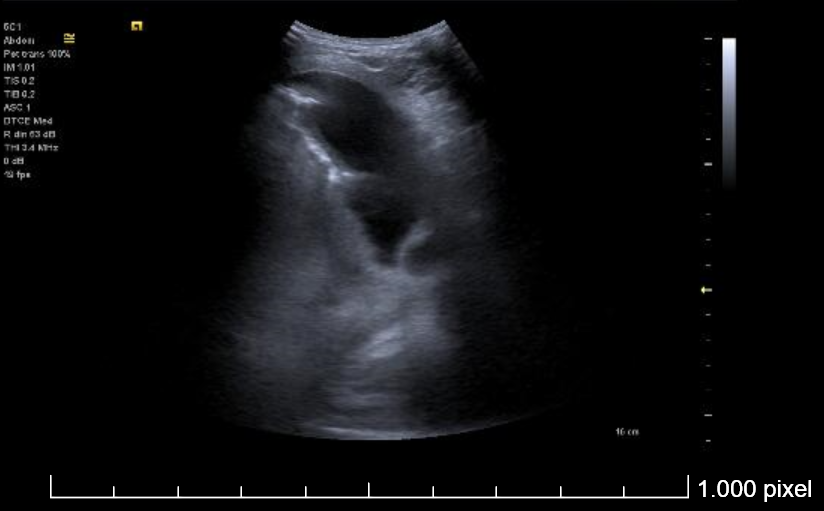

Derrame pleural izquierdo de 4 espacios intercostales, libre, hipoecogénico, sin ecos internos. Lóbulo pulmonar inferior izquierdo con imagen de patrón mixto (Intersticial y consolidación).

Se realiza toracocentesis diagnóstica y evacuadora con la paciente en decúbito lateral derecho. Se drenan un total de 550 cc en total de LP serohemático (pH en gasómetro 7.58).